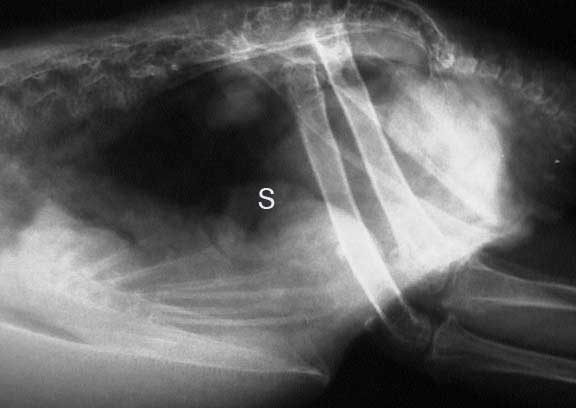

Another diagnostic test helpful in Psittacosis is radiology because it allows us to visualize internal organs. This bird has an enlarged spleen (S), the circular structure in the middle of its coelomic cavity. An enlarged spleen could be indicative of Psittacosis.